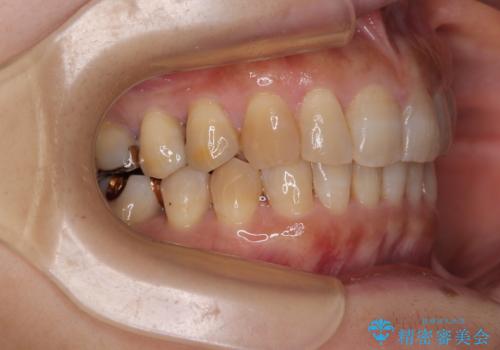

ディープバイトと前歯のデコボコ インビザラインによる矯正治療

- 前歯のディープバイトと叢生を気にして来院された患者様です。

目立ちにくい装置を希望されていたため、ワイヤー装置とインビザラインを提案したところ、インビザラインを希望されました。

下顎大臼歯が手前に倒れていたため、起き上がらせることで咬み合わせ高さを挙上し、ディープバイトと叢生を改善することとしました。

インビザライン特有の奥歯の噛みにくさが治療後半に発言しましたが、無事に終了させることができました。